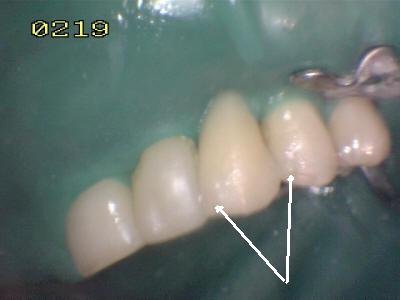

Cementado con la goma dique.  Observe los excesos de cemento de resina de curado dual (flechas blancas)

Vista palatina: Debe chequear la oclusión en céntrica y excéntrica